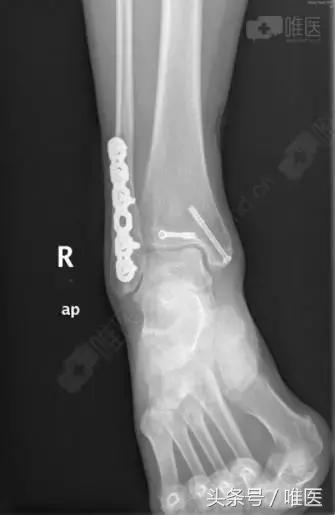

治疗后影像

全身麻醉成功后,取左侧卧位,右下肢常规消毒铺巾,右外踝后外侧切口长约8cm切开皮肤、深筋膜,自拇长屈肌及腓骨长短肌间隙进入,暴露外踝及后踝骨折块,复位后踝骨折块后予克氏针临时固定,纠正腓骨远端骨折外移及短缩畸形,克氏针临时固定,透视外踝及后踝骨折复位良好,取合适长度的后侧解剖锁定钢板螺钉牢固固定外踝,空心螺钉固定后踝,再次透视骨折复位及内固定位置良好,冲洗缝合外侧伤口,取仰卧位,右内踝弧形切口切开暴露内踝骨折块及内侧间隙,术中见内踝骨折移位,内侧间隙内碎骨块游离,清理内侧间隙,复位内踝骨折后予导针固定,透视骨折复位及导针位置良好,取34mm长度的4.0 空心螺钉牢固固定,透视骨折复位及内固定位置良好,冲洗伤口,缝合,术中出血约100ml,未予输血。术中伤口予罗哌卡因+得宝松局部镇痛治疗。手术顺利,病人送PACU。